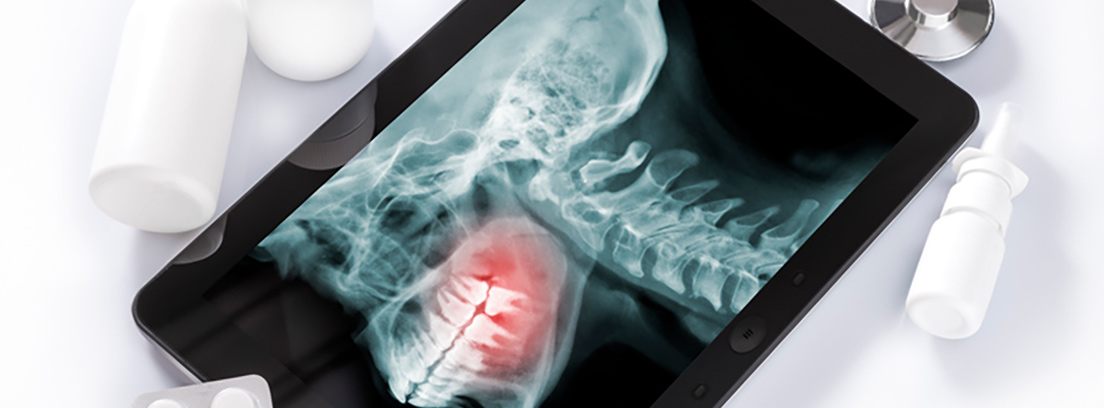

¿Qué es el cáncer oral?

El tipo de cáncer oral más frecuente es el llamado epidermoide o de células escamosas llegando al 90% de los cánceres orales. El 10% restante engloba una gran variedad de neoplasias malignas: melanoma, adenocarcinoma de glándulas salivales menores, tumores odontogénicos malignos, cáncer del seno maxilar, histiocitosis de células de Langerhans, sarcoma de Kaposi, linfomas, leucemias, mieloma y metástasis.